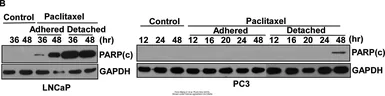

The data was published in the journal Oncotarget in 2016. PMID: 27034167

The data was published in the journal Oncotarget in 2016. PMID: 27034167

The data was published in the journal Oncotarget in 2016. PMID: 27034167